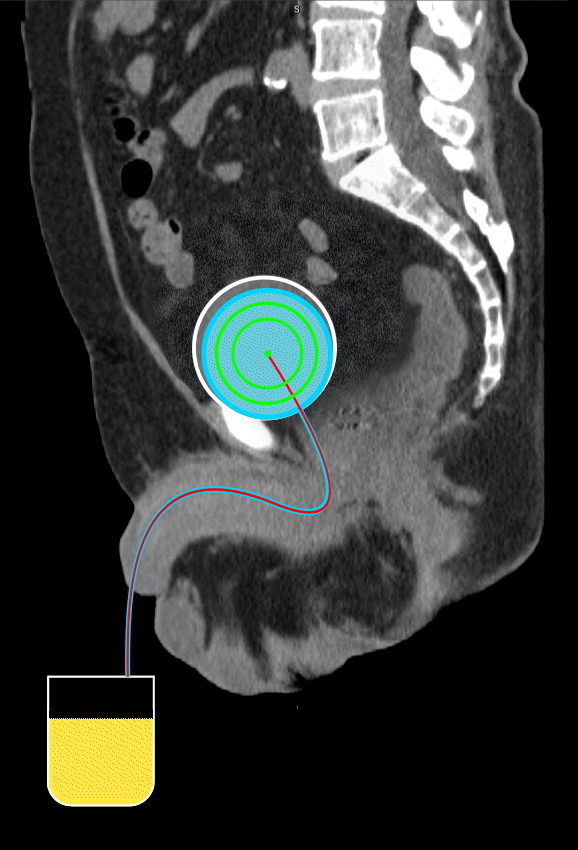

This inflatable device holds the bladder in a consistent shape for accurate placement of radiation sources while shielding surrounding organs. It addresses a major limitation in bladder cancer treatment by enabling targeted brachytherapy despite the bladder’s variable geometry. Inserted and removed via the urethra, it offers a less invasive option for patients unsuitable for bladder removal. This approach could reduce recurrence, improve comfort, and open new pathways for intravesical drug delivery